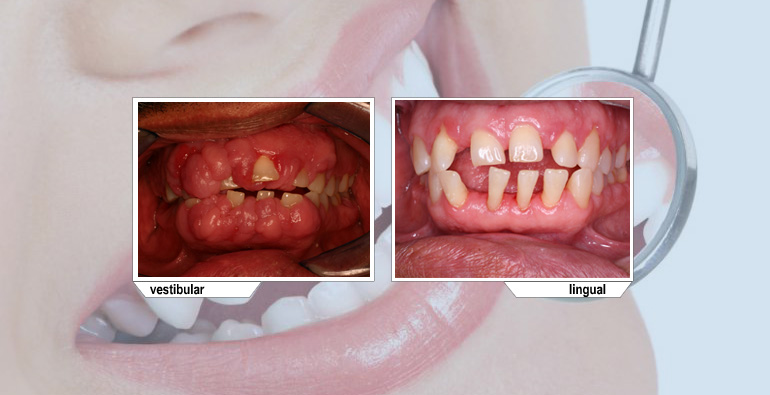

Agrandamiento por medicamentos.

Algunos medicamentos pueden causar hiperplasia gingival, en esos casos es necesario retirar el tejido por medio de cirugía.

En casos de agrandamiento gingivales este tratamiento puede resultar el ideal para volver a tener una encía con características normales.